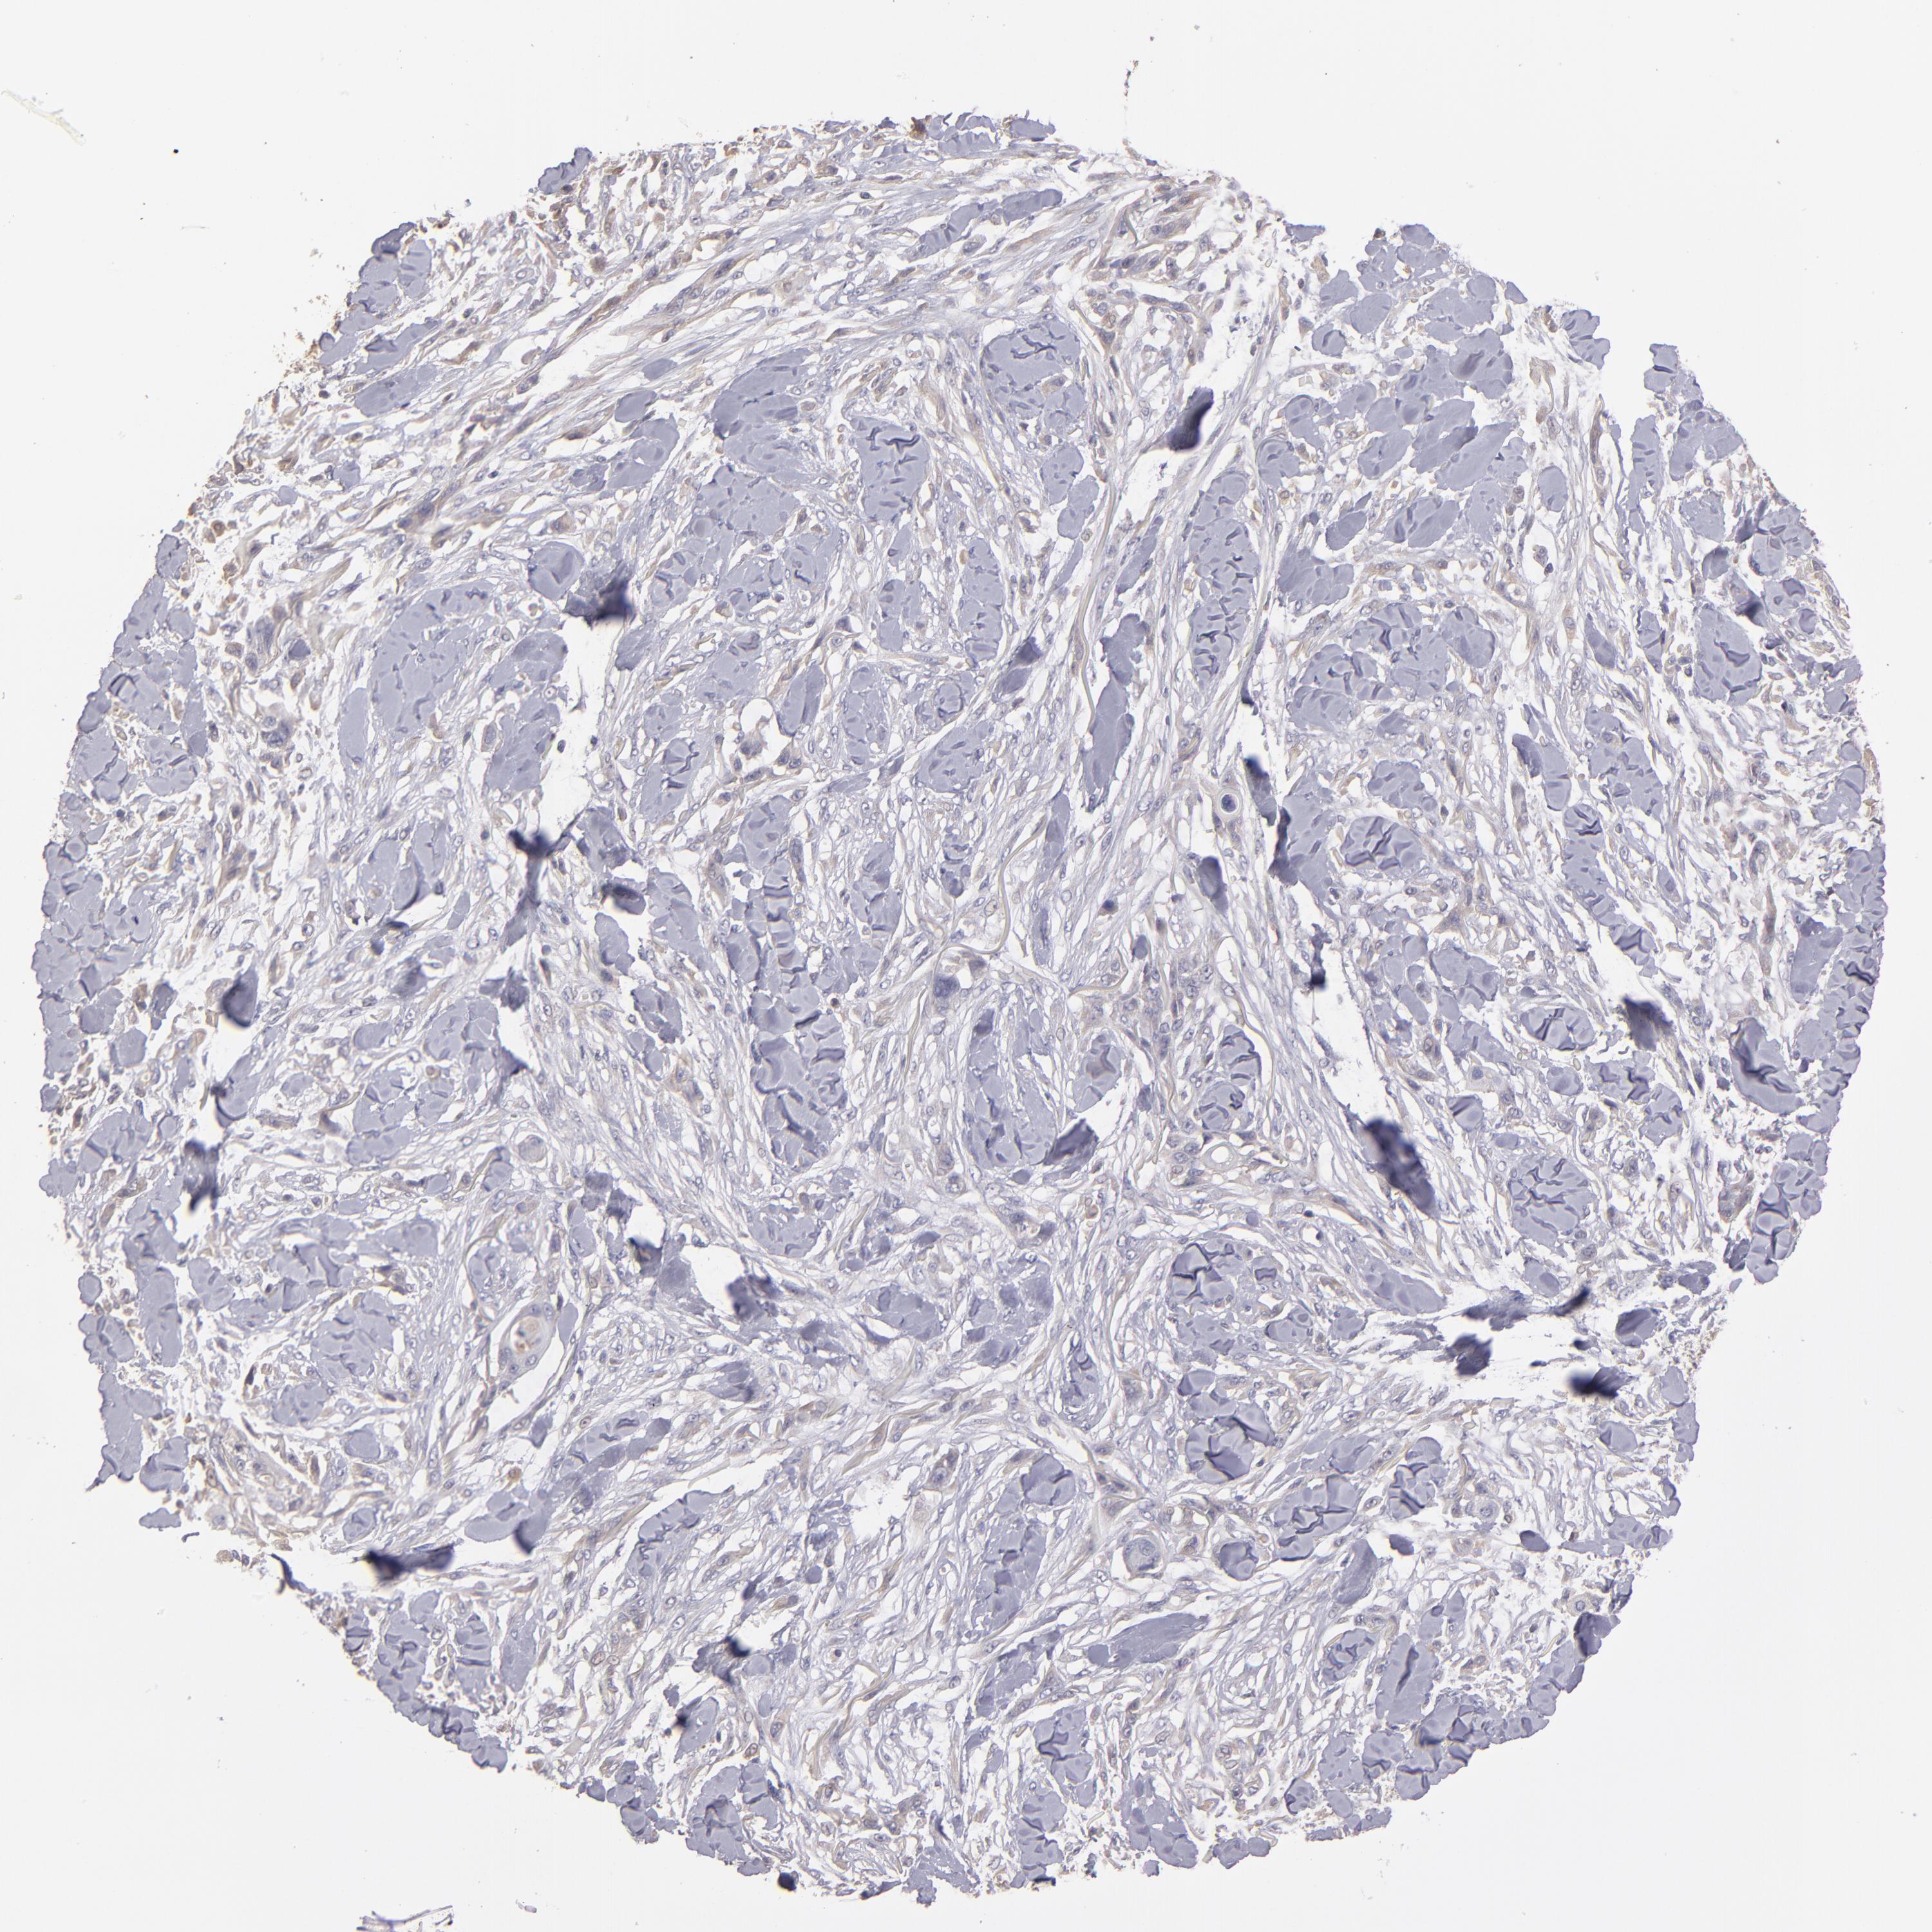

SKIN CANCER - Protein expressioni

A mouse-over function shows sample information and annotation data. Click on an image to view it in a full screen mode. Samples can be filtered based on level of antibody staining by selecting one or several of the following categories: high, medium, low and not detected. The assay and annotation is described here.

Antibody staining in the annotated cell types in the current human tissue is reported as not detected, low, medium, or high, based on conventional immunohistochemistry profiling in selected tissues. This score is based on the combination of the staining intensity and fraction of stained cells.

Each image is clickable and will lead to virtual microscopy that enables deeper exploration of all samples and also displays staining intensity scores, fraction scores and subcellular localization as well as patient and tissue information for each sample.

Antibody HPA003011

Squamous cell carcinoma, NOS